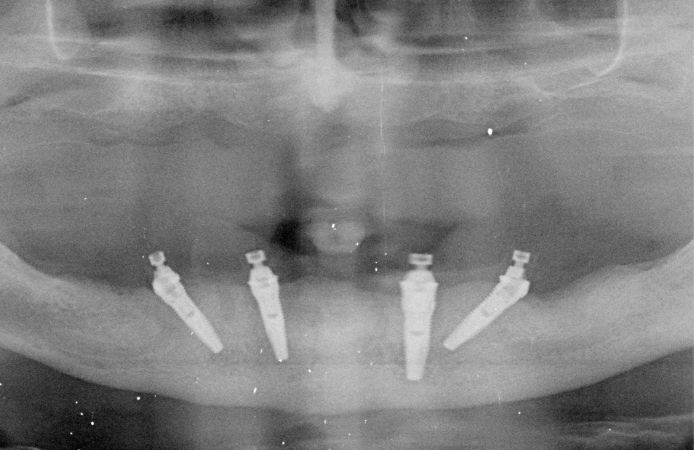

Figure 1.

Figure 2.

Figure 3.

Figure 4.